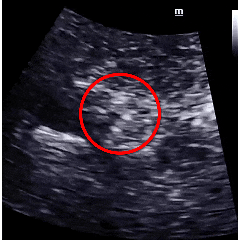

术后1个月及3个月复查时超声提示:房间隔可见封堵器回声,封堵器“三明治”结构完整,轮廓清晰,位置固定,无残余分流,无周围其他结构异常。

术后1月随访超声